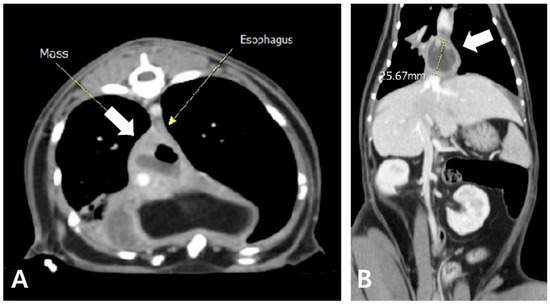

2. Case Description